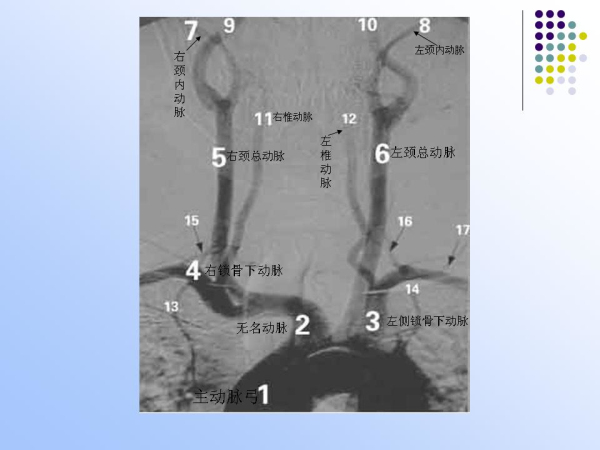

【治疗脑血管病的新技术:血管内介入治疗】—神经内科脑卒中筛查与防治办公室

神经内科

脑卒中筛查与防治办公室